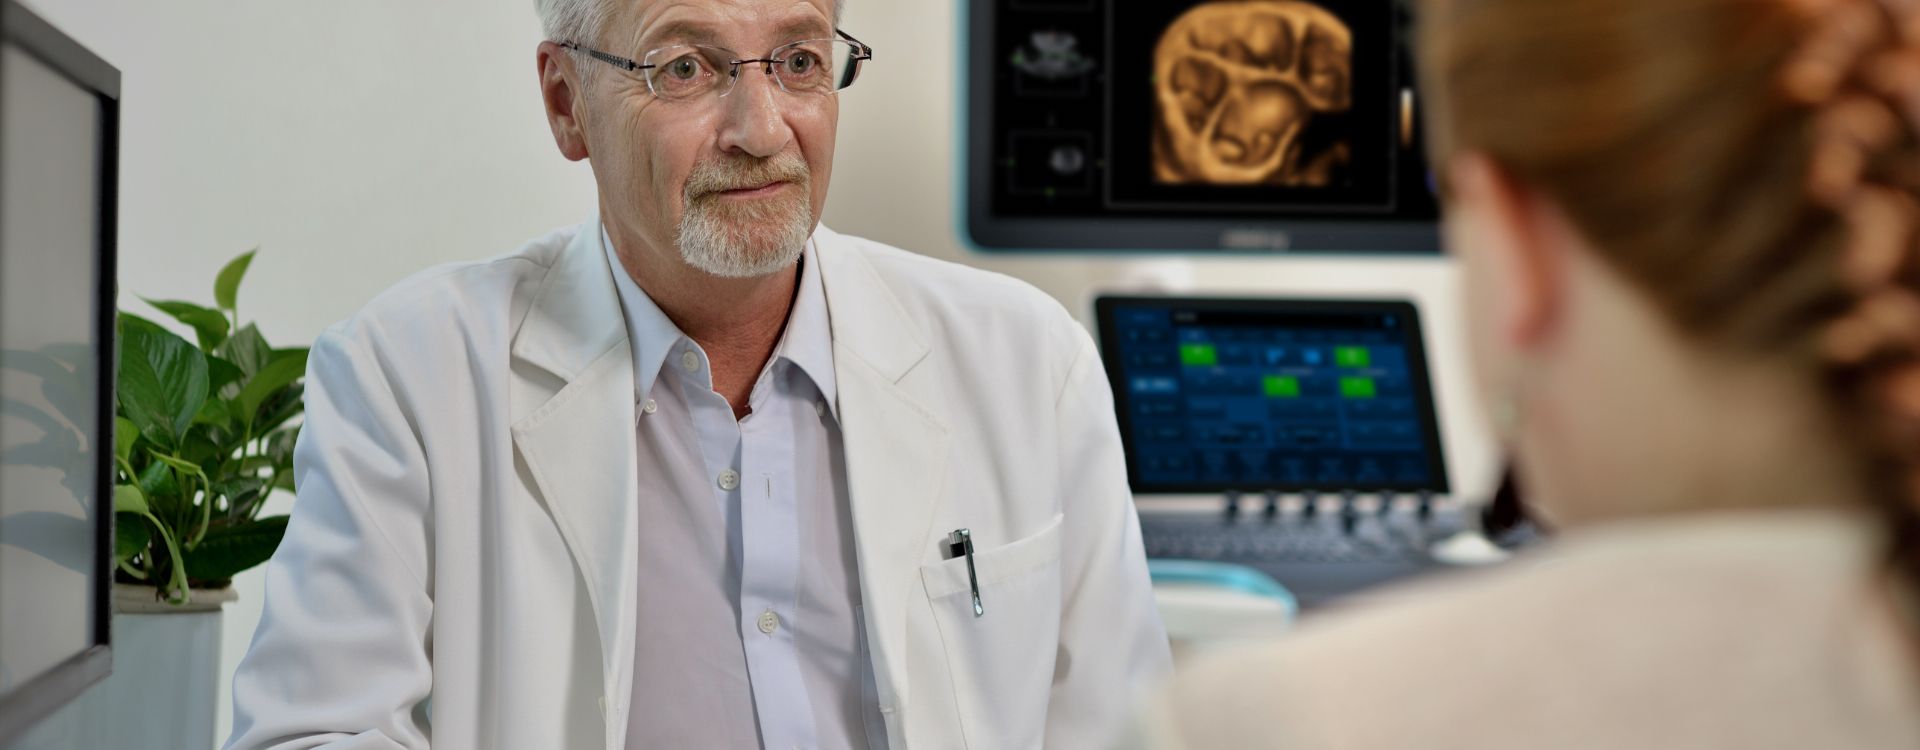

La gamme d'imagerie gÊnÊrale Resona de Mindray aide les cliniciens à obtenir des rÊsultats de diagnostic plus prÊcis et des traitements plus efficaces gr?ce à une gamme de sondes complète et à des outils cliniques avancÊs efficaces.

L'environnement mĂŠdical devient de plus en plus complexe, avec toujours plus de cas difficiles et une charge de travail toujours plus importante.